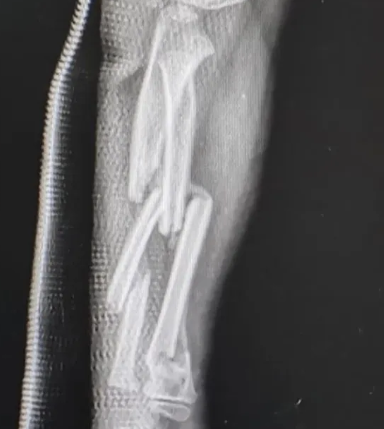

• 科研人员研发治疗粉碎性骨折的“胶水”

浙江大学医学院附属邵逸夫医院研发出能够在人体血液环境中实现即时强效黏合的骨胶水材料,为粉碎性骨折患者带来新的治疗模式。

骨折是临床上常见的损伤,目前,主要应用螺钉、钢板等金属内固定物进行治疗。“对于伴随众多细小碎骨块的粉碎性骨折,临床治疗仍面临巨大挑战。”浙大邵逸夫医院骨科主任范顺武介绍,应用传统金属固定方法,固定小骨片过程不仅费时费力,而且易导致骨碎片在操作中丢失或被吸收,最终影响骨愈合。